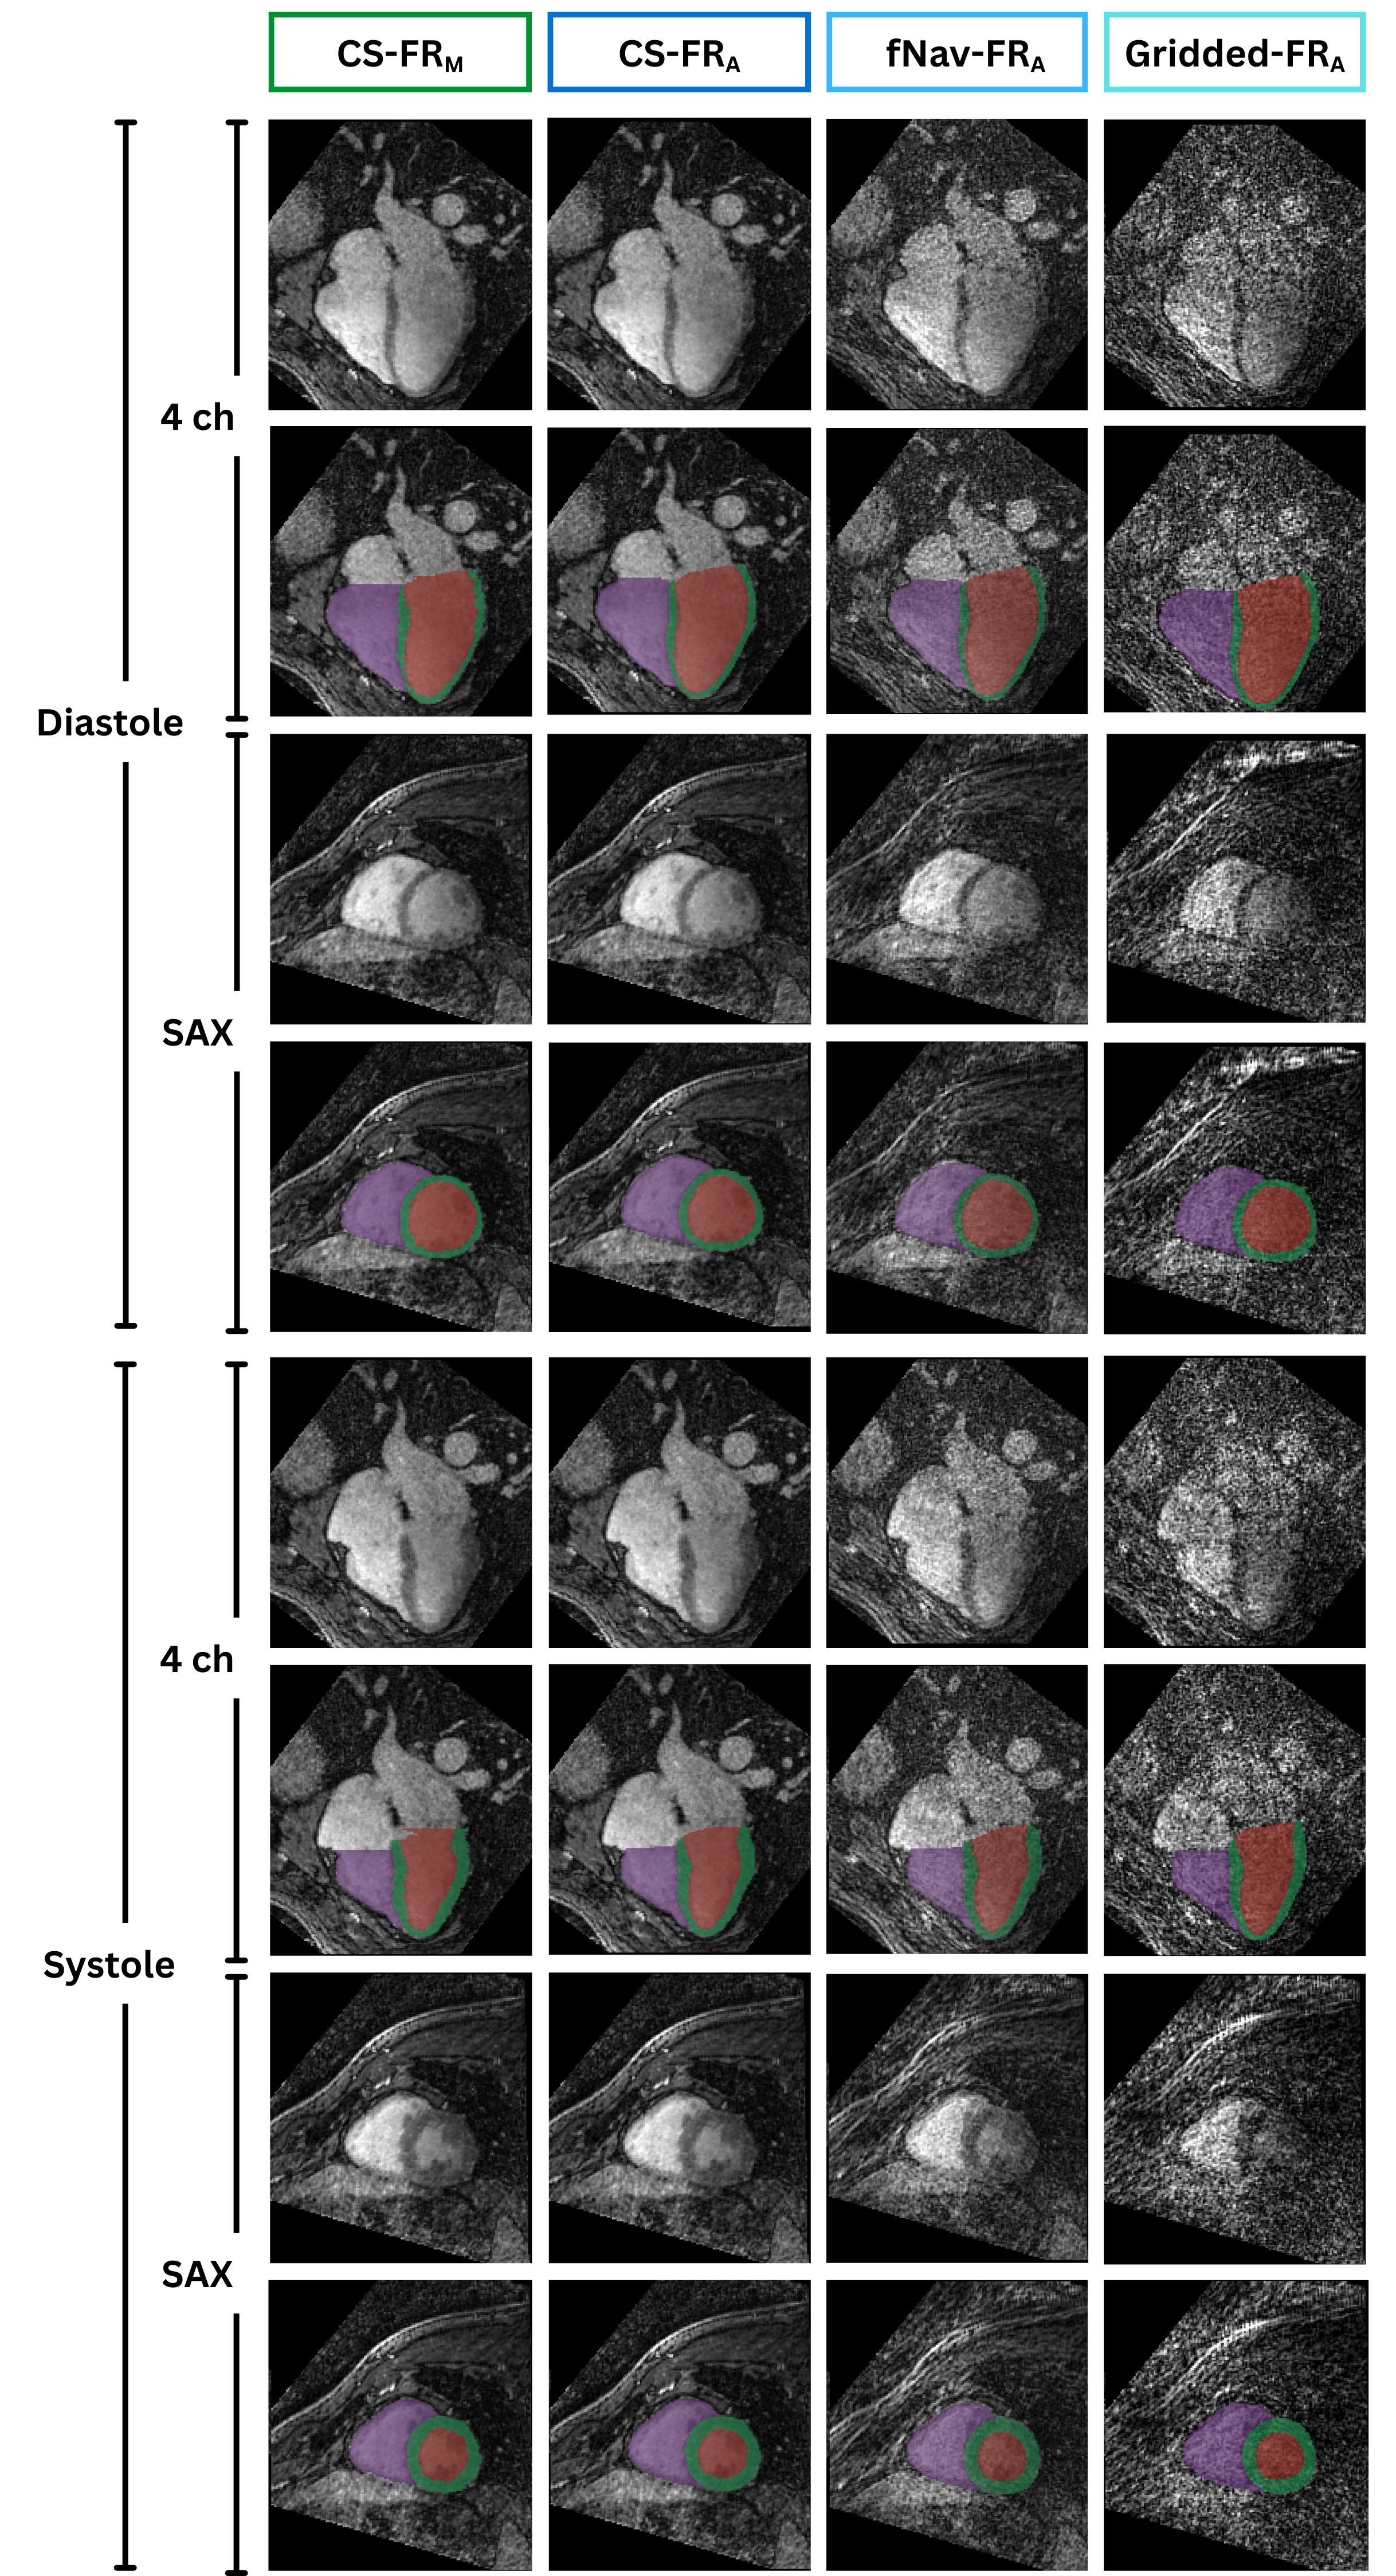

Results: All three automatic segmentations closely matched ground-truth (Fig. 1) with strong geometric accuracy (Table 1). They also demonstrated strong ejection fraction agreement, with negligible bias ( < 1 mL), narrow limits of agreement, and high ICC ( >0.96) (Fig. 2A–C). Myocardial volume was conserved across cardiac phases in all automatic segmentations and did not differ significantly from the ground-truth segmentation (Fig. 2D).

Conclusion: We demonstrated that the proposed DL segmentation models deliver clinically equivalent performance on rapidly reconstructed gridded and fNav images compared to the high‐quality CS reference. These results indicate that CS is not necessary for accurate whole-heart delineation, enabling immediate post-acquisition analysis. The models have already been implemented for on-scanner deployment. Future prospective studies should quantify their impact on workflow efficiency and diagnostic accuracy to pave the way for FR whole-heart cardiac MRI in clinical routine.